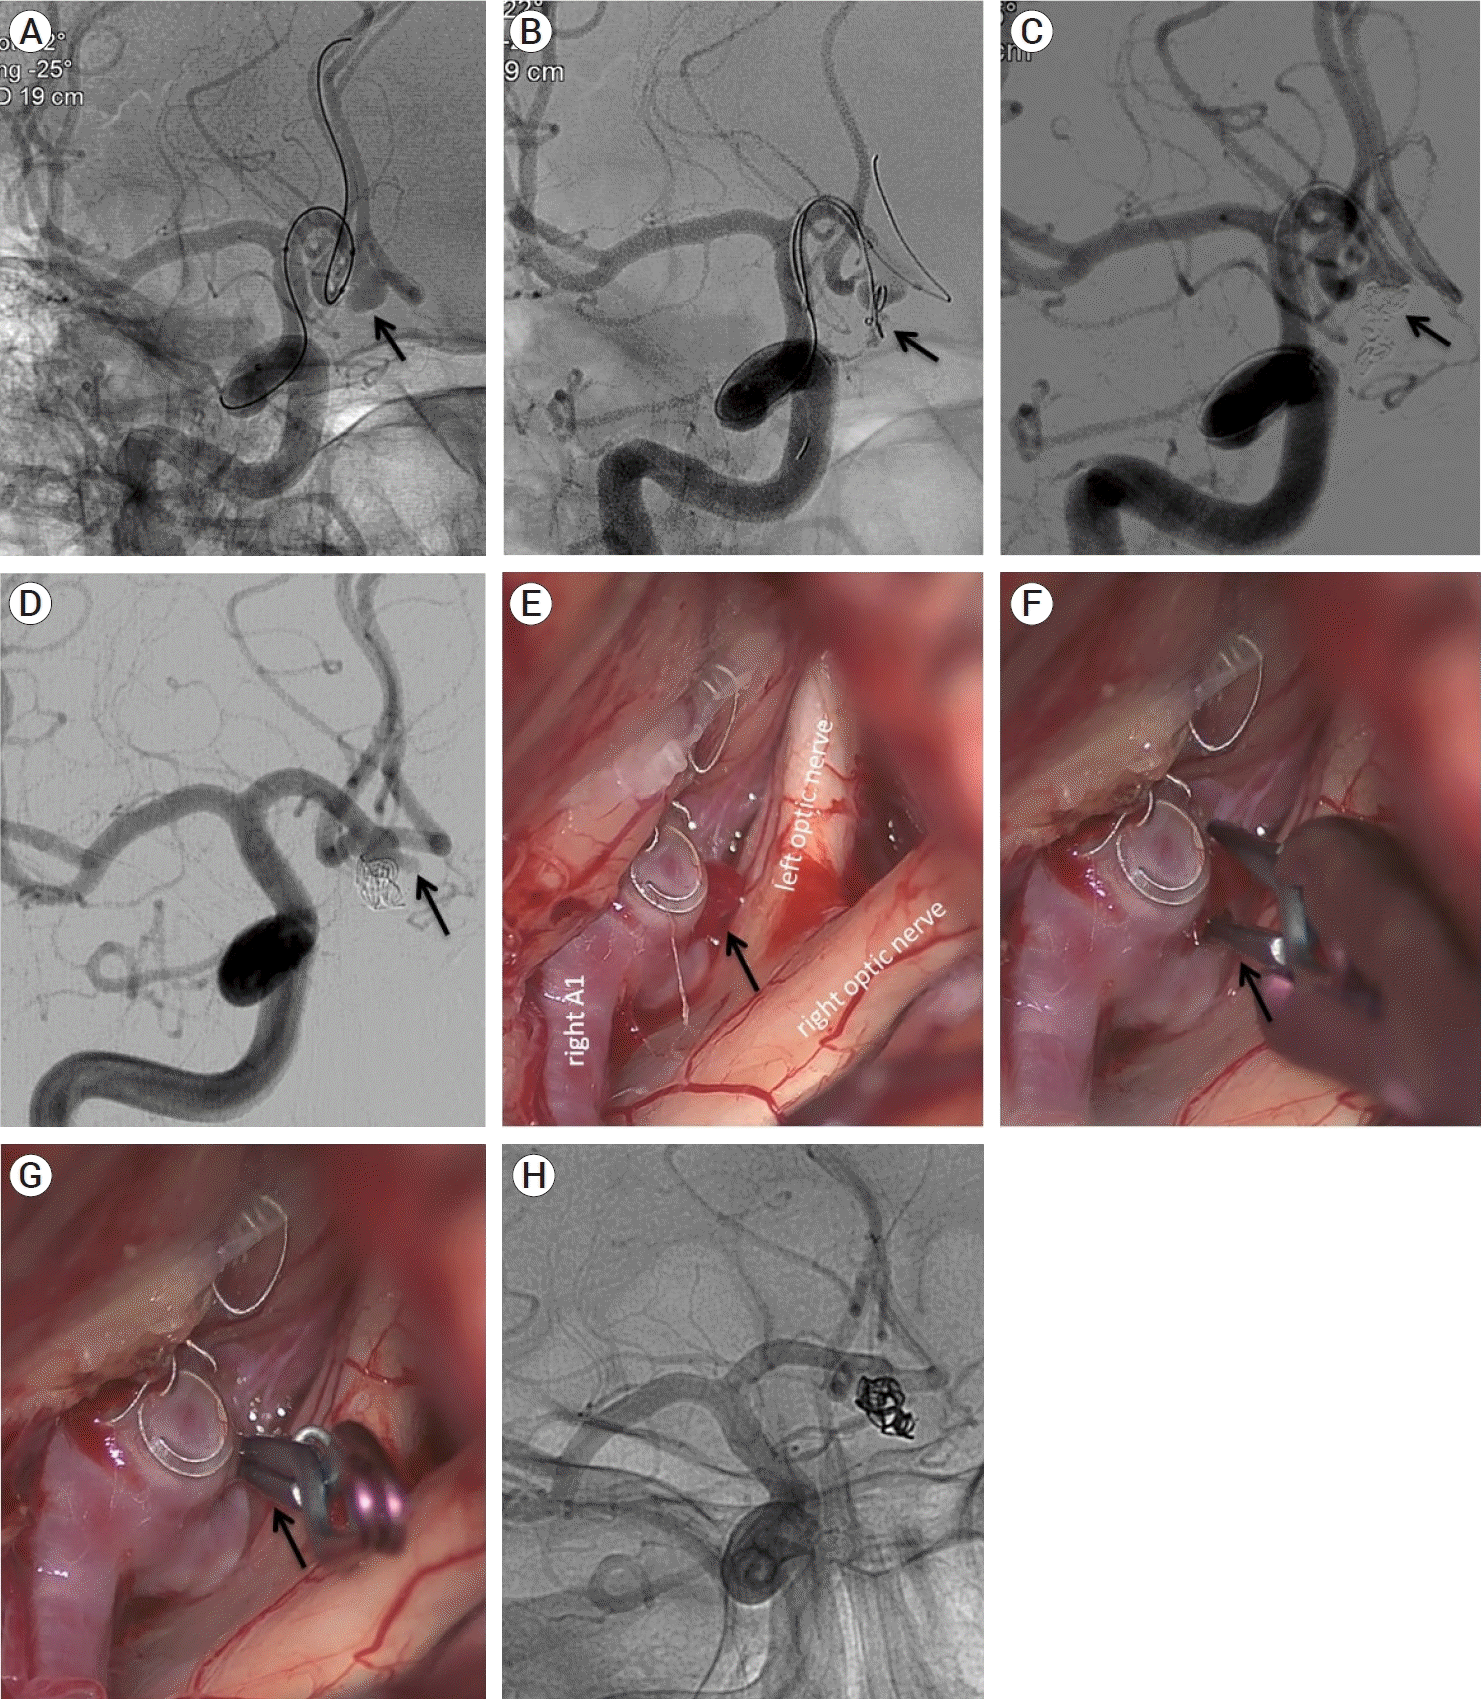

A 63-year-old man was admitted lethargic due to a 4 mm ruptured wide-neck ACoA aneurysm (A, black arrow). During embolization using balloon-assisted technique, re-rupture of the aneurysm occurred after deployment of the first coil (B, black arrow). Further embolization with coils, keeping the microcatheter in place, resulted in complete aneurysm occlusion from outside to inside (C, black arrow). The patient experienced a full recovery and was discharged after 15 days. Nevertheless, a follow-up angiography revealed a newly formed aneurysm projection (C, D, black arrow), which was treated by microsurgical occlusion. Intraoperative view shows the new aneurysm bleb (E, black arrow). A mini-clip was used to occlude the new bleb (F, G, black arrow) followed by aneurysm wrapping. Postoperative angiogram demonstrated complete occlusion of the aneurysm (H, black arrow). No perioperative complications occurred.

(A) DSA (subtracted view) shows a ruptured wide-neck ACoA aneurysm (black arrow). (B) During embolization using balloonassisted technique penetration of the aneurysm occurred after deployment of the first coil (black arrow). (C) Further embolization with coils resulted in complete aneurysm occlusion (black arrow). (D) A FU angiography revealed a newly formed aneurysm projection (black arrow). (E) Intraoperative view shows the aneurysm bleb (black arrow). (F, G) A mini-clip has been used to occlude the new bleb (black arrow) followed by aneurysm wrapping. (H) Post-surgical angiogram shows complete occlusion of the aneurysm (black arrow). DSA, digital subtraction angiography; AcoA, anterior communicating artery